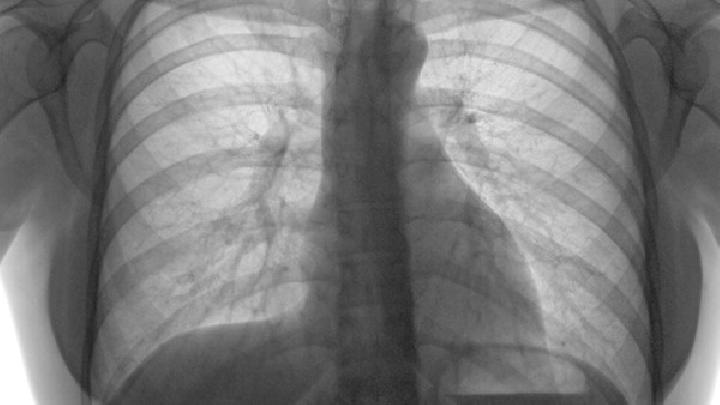

巨细胞病毒肺炎缓进型移植后3~4症状与急进型相似,但进展缓慢,症状轻微,死亡率低。可并发网膜炎结肠炎、胆管炎、食管炎、全身病毒血症、继发细菌和真菌感染。

巨细胞病毒肺炎症状